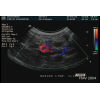

La vascularisation

Durée. 2:54                 Dr Guy Beauregard